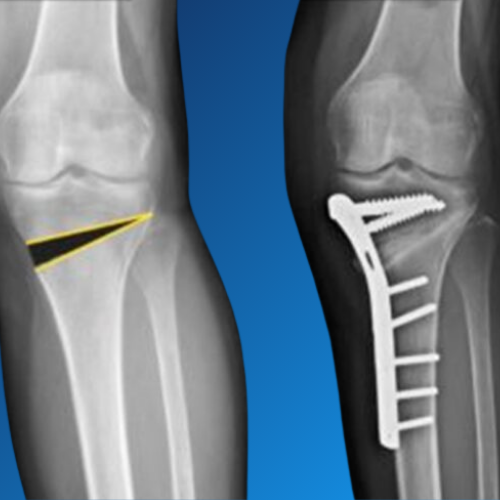

Knee Osteotomy is a specialized orthopaedic procedure aimed at realigning the knee joint to relieve pressure from damaged cartilage and reduce pain caused by arthritis or deformity. Dr. Nishant Bhatia offers expert knee osteotomy surgeries for patients seeking joint preservation and improved mobility.

This procedure is often recommended for younger or active individuals with early-stage arthritis affecting one side of the knee. By reshaping the tibia or femur, knee osteotomy shifts the body’s weight away from the damaged area, delaying the need for total knee replacement.

• Medial Opening Wedge Technique

Using precision planning, surgical guides, and advanced fixation techniques, Dr. Bhatia ensures accurate realignment, stable healing, and faster rehabilitation. His approach focuses on preserving the natural knee joint and restoring optimal function.